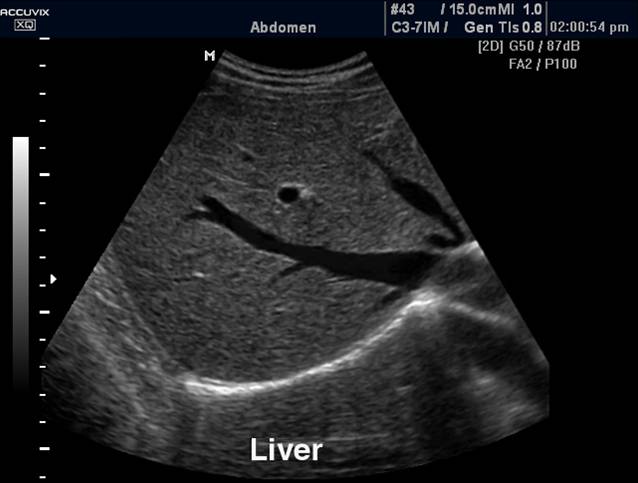

正常肝脏声像图:M型超声(右图)示靠近第二肝门附近的肝实质随心动周期变化而有伸缩,提示肝质地柔软